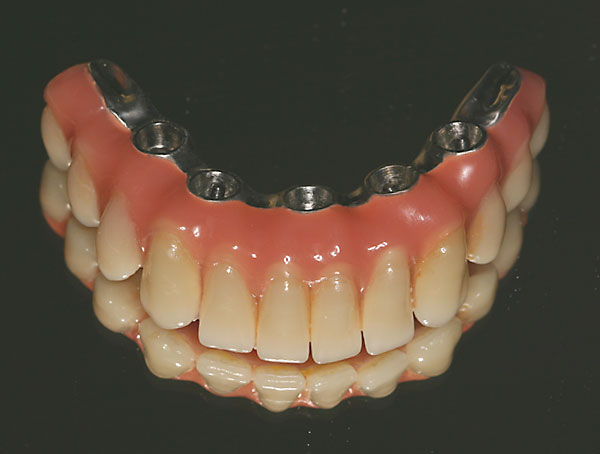

Unterkiefer, fixe Brücke

![]() |